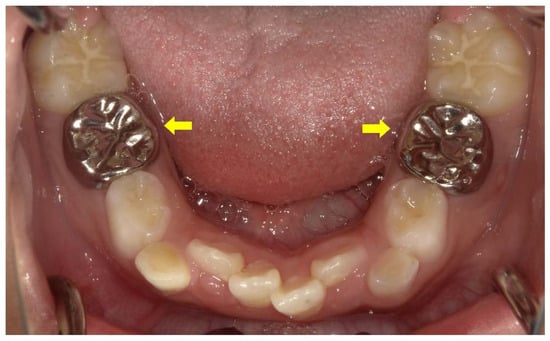

- Wato, K.; Okawa, R.; Matayoshi, S.; Ogaya, Y.; Nomura, R.; Nakano, K. X-linked hypophosphatemia diagnosed after identification of dental symptoms. Ped. Dent. J. 2020, 30, 115–119. [Google Scholar] [CrossRef]

- Okawa, R.; Hamada, M.; Takagi, M.; Matayoshi, S.; Nakano, K. A Case of X-Linked Hypophosphatemic Rickets with Dentin Dysplasia in Mandibular Third Molars. Children 2022, 9, 1304. [Google Scholar] [CrossRef]